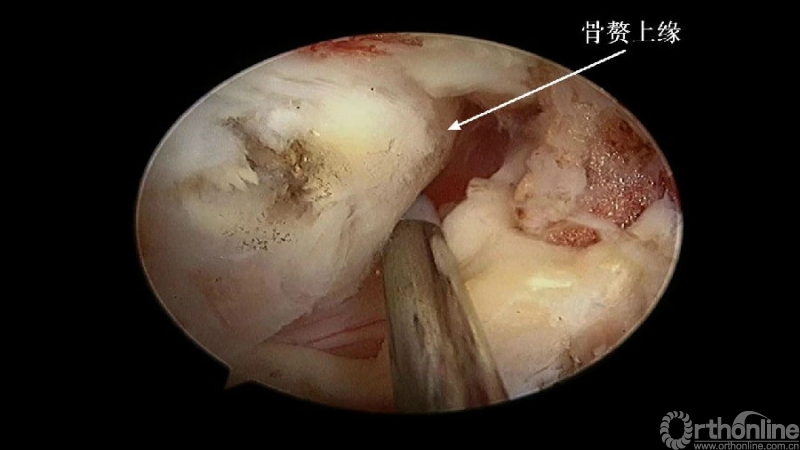

2.显露骨赘的内侧面及上下缘;

2. 术中骨赘的界限?